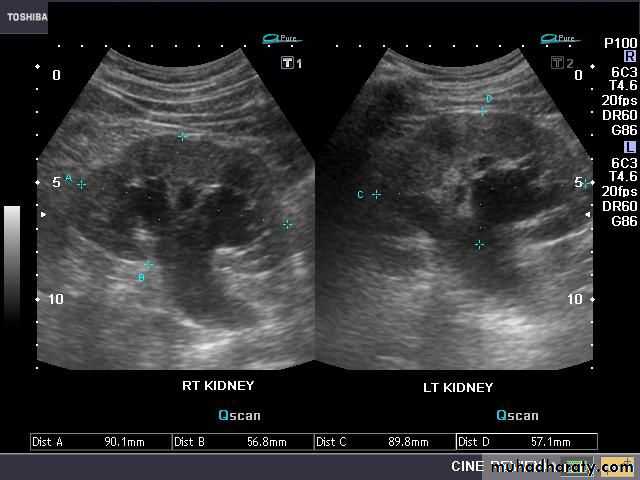

Abdominal x-ray typically reveals a large soft tissue opacity displacing bowel shadowNormal US of the renal system

hydronephrosis